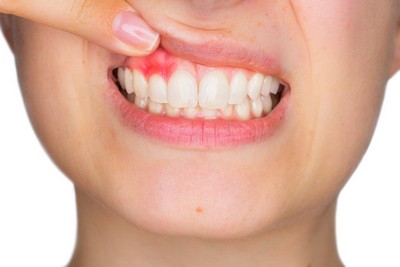

Неприятный запах изо рта, воспалённая десна, субфебрильная температура, изменившаяся по цвету эмаль, возросшая чувствительность к холодному и горячему и незначительно увеличенные шейные лимфоузлы — дополнительные симптомы, которыми часто сопровождается пульпит.

- Пародонтит средней или тяжёлой стадии. В этом случае инфекция попадает в пульпу через корневую систему либо соединительную ткань.

Периодонтит и его определение в стоматологии

Гнойный воспалительный процесс у верхушки корня. Токсины и микроорганизмы проникают в периодонтальное пространство, и инфекция стремительно прогрессирует в тканях периодонта.